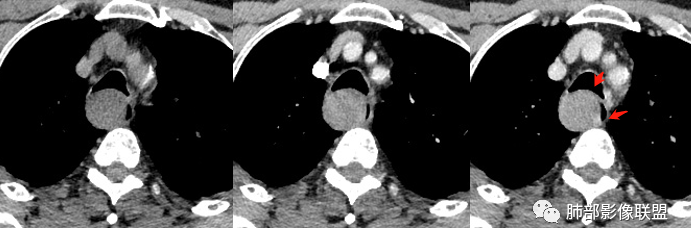

右后上纵隔软组织肿块,与食管关系密切,跨食管壁内外生长,长轴与食管走行一致,食管明显狭窄,邻近气管受压,密度相对均匀,渐进性强化,首先考虑食道来源平滑肌瘤,鉴别神经鞘瘤。

右后上纵隔气管食管沟肿块,跨食管壁内外生长,长轴平行食管,食管管腔明显狭窄,邻近气管受压,密度均匀,渐进性强化,定位考虑食道来源,定性考虑平滑肌瘤,鉴别血管瘤或血管球瘤,恶性可能性不大

晨读:男性,体检发现右后纵隔占位,CT示右后纵隔梭形软组织肿块,局部与食管壁分界不清,压迫气管与食管,平扫密度均匀,增强轻度不均匀渐进性强化,内部可见片状低密度区,考虑为1、食管来源平滑肌瘤。2、神经鞘瘤